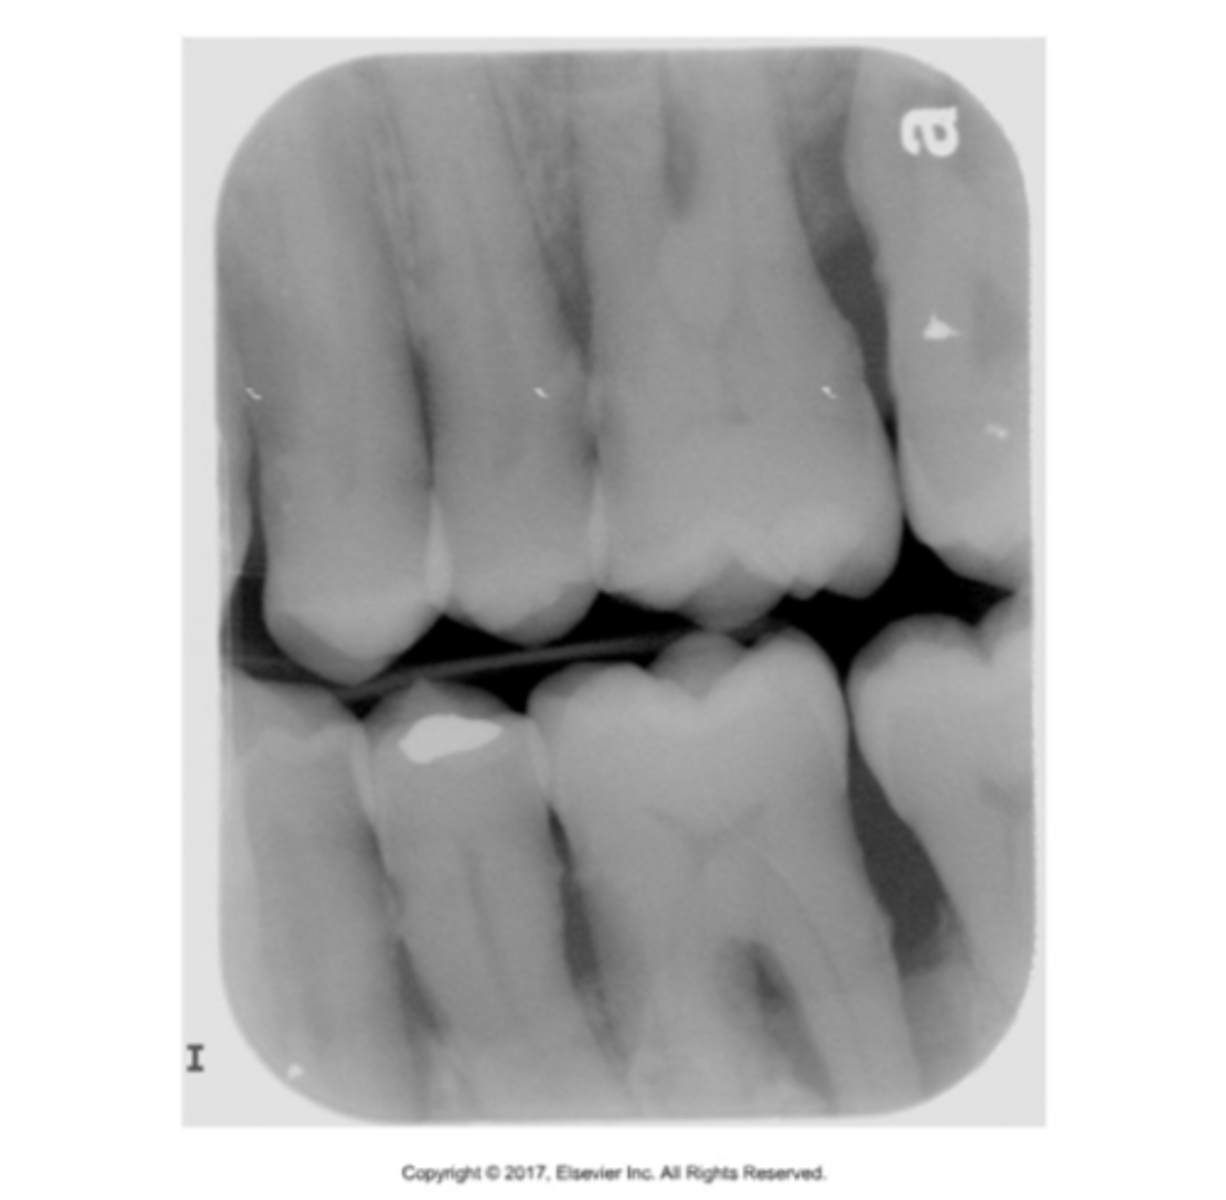

incorrect placement of premolar bite wing

distal surfaces of the canine are not visible of the image

receptor too far back

make sure anterior edge of receptor is at the midline of the mandibular canine